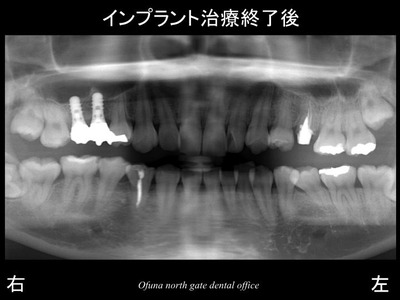

以下は 治療前 と 治療後 の比較です。

以下は被せ物を装着した治療後です。